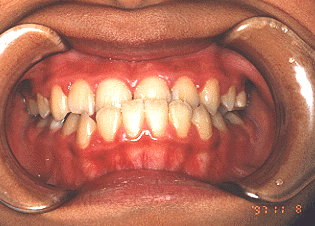

下の前歯が出ている咬み合わせです。放置していると 前歯がぐらついたり、下顎が前に出て顔貌に影響する場合 もあります。